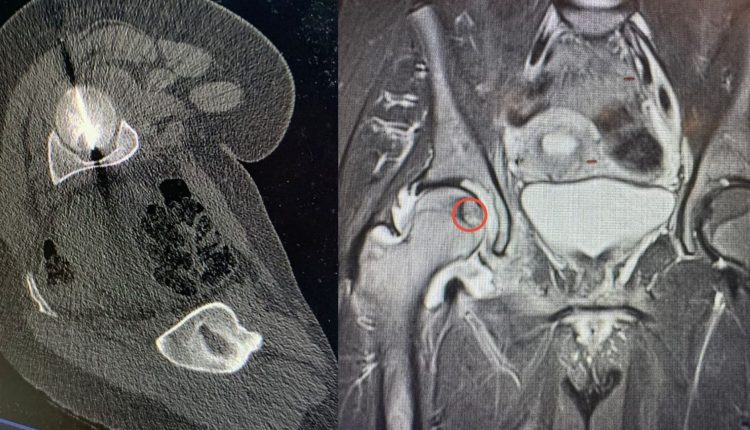

حصادنيوز – عمّان – نفّذ مستشفى الجامعة الأردنية تدخلاً علاجياً نوعياً في قسم الأشعة، تمكّن خلاله فريق طبي متعدد التخصصات من معالجة ورم عظمي يقع في منطقة بالغة الحساسية داخل رأس عظم الفخذ لمريض في الثلاثين من عمره، وهي منطقة تُعد من أكثر المواقع صعوبة في الوصول إليها بالطرق الجراحية التقليدية.

وكان المريض يعاني من آلام شديدة قيّدت قدرته على الحركة والقيام بمهامه اليومية، الأمر الذي تطلّب تدخلاً دقيقاً باستخدام تقنيات متقدمة تفوق إمكانات الجراحة المفتوحة.

وأوضح الدكتور البطوش أن الفريق نجح في الوصول بدقة بالغة إلى مركز الورم اعتماداً على تقنية التصوير الطبقي المحوري (CT Scan)، قبل إجراء الكي الحراري باستخدام المايكروويف، وهي من أحدث التقنيات العالمية في علاج أورام العظام دون الحاجة لجراحة مفتوحة.